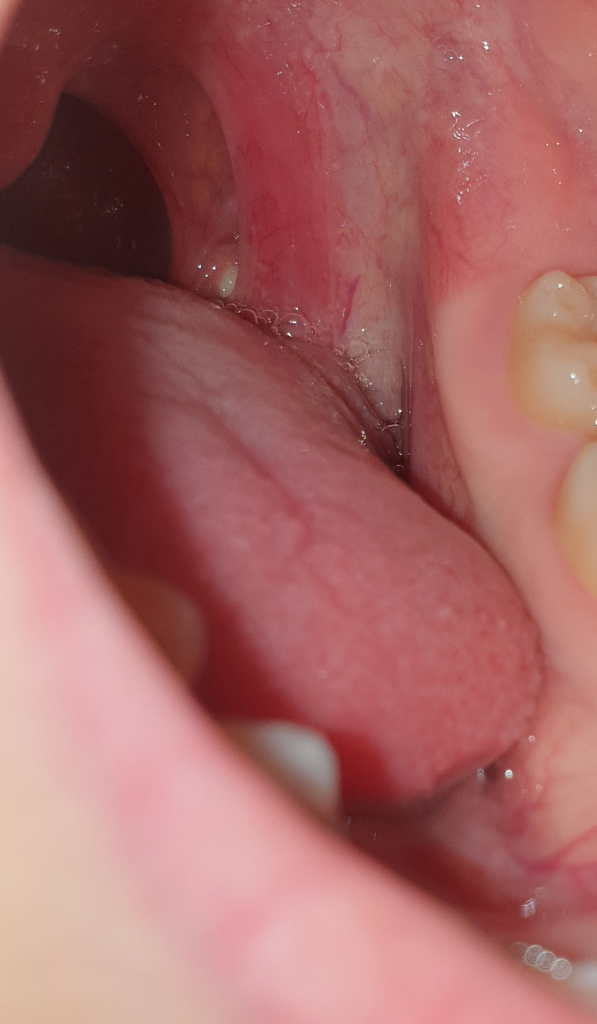

편도에 뭐가 생긴건가요? 하얀색 동그라미

저기에 하얀색 이빨? 같이 뭐가 동그랗게 났는데 편도결석인가요? 아니면 다른 질병인가요?

이걸 치료를 받아야하나요? 만약 치료가 필요하다면 어느 병원을 가야하죠?

• 1번 째 사진

사진만으로는 다소 제한적이나 편도 결석이 생각 됩니다.

편도 결석은 편도 혹은 편도선에 있는 작은 구멍들에 음식물 찌꺼기와 세균이 뭉쳐서 생기는 쌀알 크기의 작고 노란 알갱이를 말하며 이름에 결석이라고 붙어 있지만 대부분 돌처럼 딱딱하지는 않습니다.

저절로 나오기도 하며 흡인 등으로 제거하는 치료를 할 수 있는데, 어느 정도 시간이 지나면 다시 생길 수도 있으며 레이저나 질산은 같은 약물로 편도에 있는 구멍을 막는 치료를 하기도 하지만, 편도 자체를 없애는 편도절제술이 가장 확실한 방법입니다. 그러나 편도결석이 있다고 모두 편도절제술을 시행할 필요는 없고, 수술의 효과와 합병증의 위험을 고려하여야 합니다.

편도염이 있을 때 종종 관찰되는 삼출물로 보입니다. 편도염을 추정할 수 있는 근거가 되는 편이고, 이비인후과에서 확인을 받아보실수 있겠습니다.

• 사진의 소견만으로 정확하게 판단하기는 어렵지만 편도의 석일 가능성이 가장 높아 보입니다. 아니라면 반대로 구내염일 수도 있겠습니다. 일단 상태 평가를 위해서 이비인후과 진료 및 검진을 받아보시길 권고드립니다.